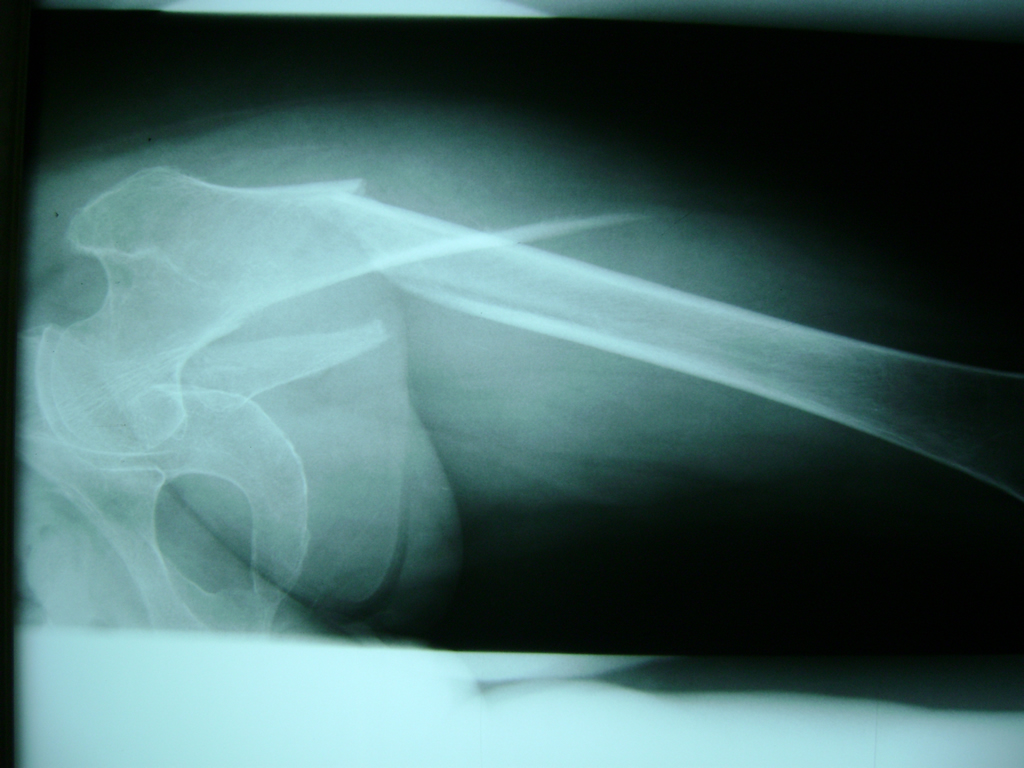

La cirugía de fractura de cadera se realiza para reparar una ruptura en la parte superior del hueso del muslo. Este hueso se denomina fémur.

Es parte de la articulación coxofemoral. Si una fractura de cadera no recibe tratamiento, es posible que deba permanecer en una silla o en la cama.